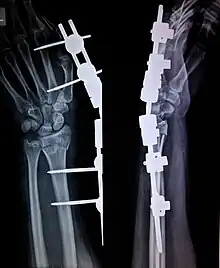

Radio de broches reliées à un fixateur externe. (sens 3)

- (Chirurgie) Tige métallique utilisée en chirurgie pour consolider ou fixer un os fracturé, une articulation.

Après son accident, on lui a posé des broches sur sa fracture.